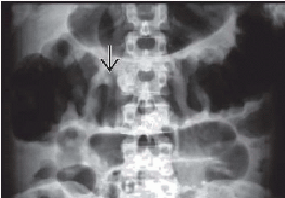

Colonic distension d'une "

ulcerative colitis " et hemorragique . Lesion est

tres grave par la presence des eruption de la

muqueuse du colon ( fleche noire ) . |

|

Image TDM en

coupe transversale colite ulceree et toxic megacolon

: La colon trans verse est tres dilate et image

irregulier de la muqueuse du colon ( fleche

blanche ) |